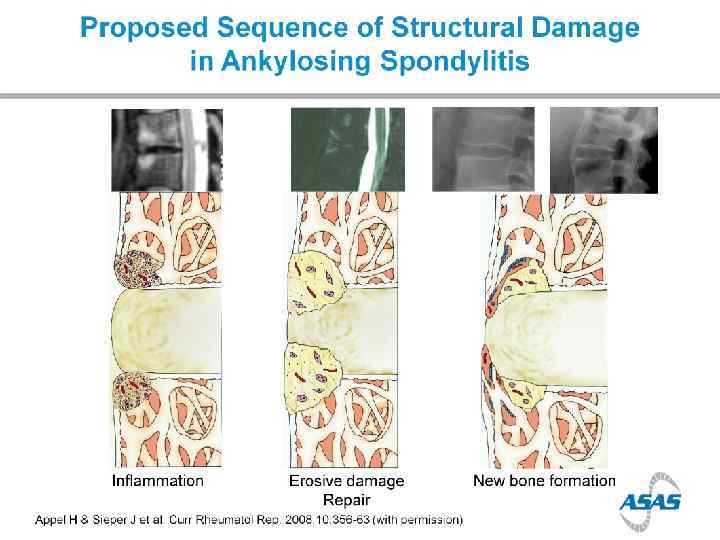

Bone formation in AS

Spine

Patient’s symptoms One half comes from inflammation, the second half comes from structural changes

Disease progression

Disease progression > in males > in smokers > in those with high CRP >>> in those with syndesmophytes at baseline

Disease progression